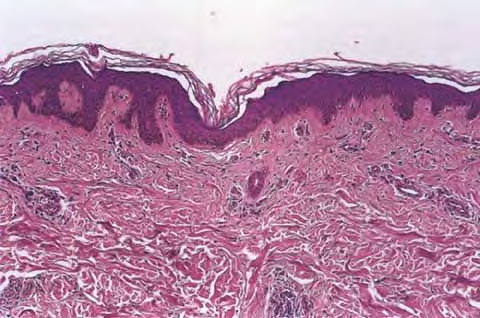

Acute discoid lupus erythematosus = الذئبة الحمامية القرصية الحادة